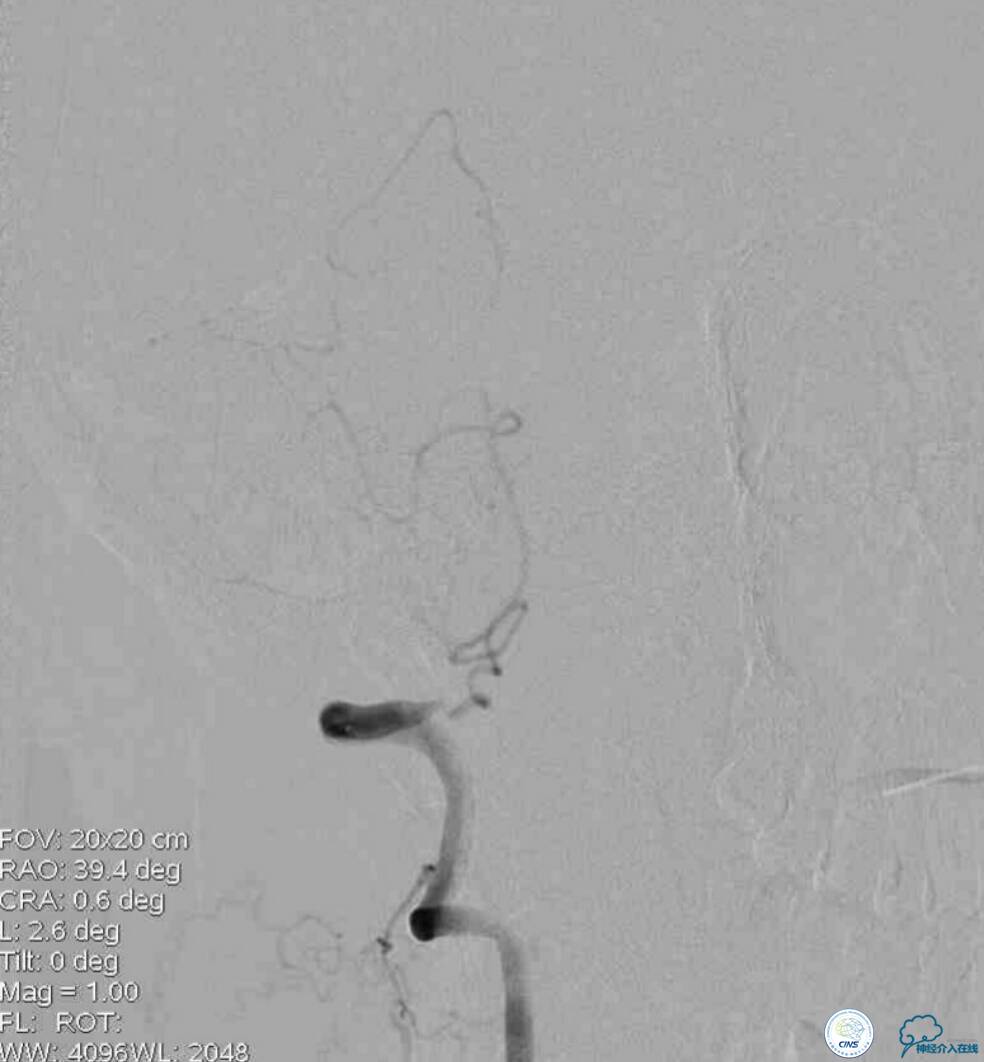

同期行DSA提示右椎动脉V4段发出右PICA后未见顺行显影(图2),左椎动脉V4段-基底动脉汇合处重度狭窄(图3),前循环向后循环的未见明显代偿(图4)。

图2

图3

图4